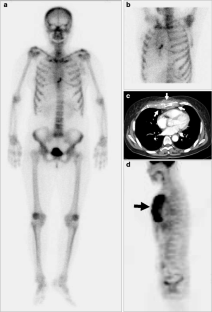

Absent Sternum as the First Manifestation of Bone Metastasis on Bone Scintigraphy

The sternum is known as a relatively common site for bone metastases by a variety of malignant neoplasms. The usual finding is increased radiotracer uptake on bone scintigraphy, and cold metastasis is distinctly unusual. In addition, total nonvisualization of the sternum presenting as bone metastasis is extremely rare. We describe two cases with similar findings (absent sternum showing no activity of the sternal segments on bone scintigraphy), which corresponded to metastatic involvement. These findings were shown to be the first manifestation of hepatocellular carcinoma in one patient and bone metastasis in another patient with ovarian cancer.

Fig. 1